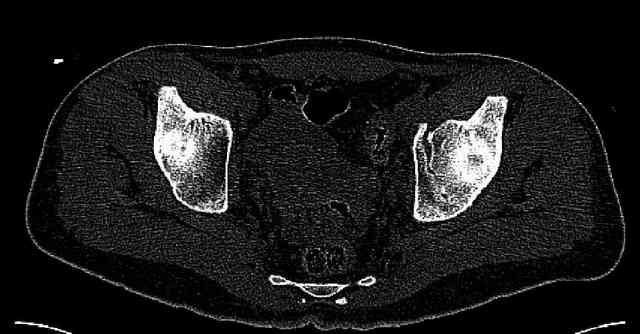

Some more images. Does it help to guess which part of the acetabulum is displaced?

Normal appearing SI joints and a healed posterior column limb... my bet's on caudal segment displacement.

The anterior element of the fracture is so low and the anterior roof arc angle must be at least 60 deg.

The posterior element is so minmally undisplaced. There is good congruence of the joint, and to top it all, 6 weeks have passed. If you consider ORIF now, I don't expect that much improvement could be accomplished. Not to mention the need for extensive approaches with their morbidity.